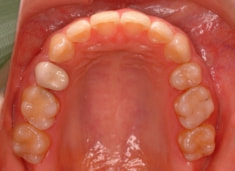

治療前